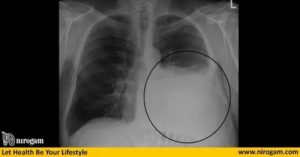

Рентгенография. Дает возможность определить наличие жидкости, если ее количество составляет от 300 — 400 мл. Также данный метод позволяет обнаружить опухолевые очаги и метастазы, которые распространились в плевральную область и лимфатические узлы. Рентгенографию осуществляют и для контроля состояния пациента после процедуры эвакуации (удаления) жидкости из легких.

- Рентгеноскопия. Проблемные участки на рентгенограмме выглядят как однородное затемнение,

Важно! От рентгеновских снимков не будет пользы при слабовыраженном заболевании, поскольку количество крови или лимфы минимально (100-200 мл).